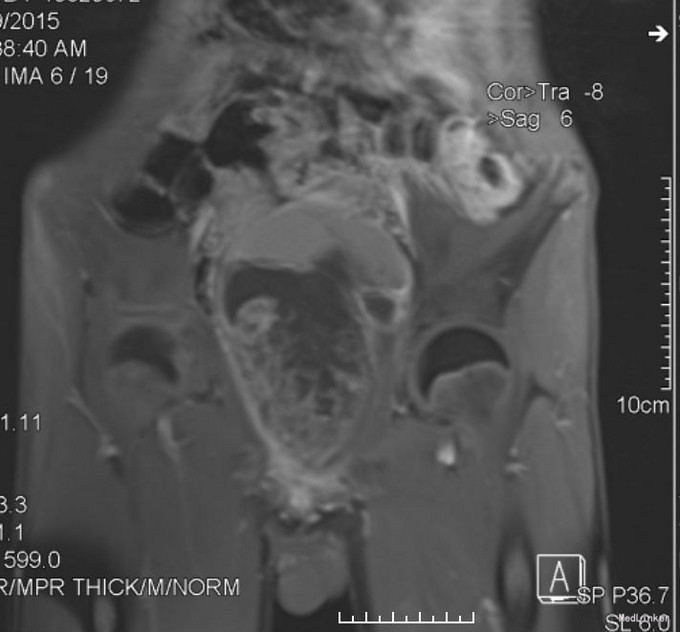

查体:下腹部膨隆,无腹壁静脉曲张,腹式呼吸存在,无胃肠蠕动波,无肠型。腹壁柔软,无压痛、反跳痛,肝脾肋下未及。肝区无叩击痛,脾区无扣击痛,下腹部可触及约12x15cm大小,质韧,边界清楚,活动度欠佳。移动性浊音(-),振水音(-)。肠鸣音5次/分。 2015-9-26 血常规:白细胞 4.9 *10^9/L ,血红蛋白 134 g/L ,血小板 272 X10^9/L 。 生化检验报告:总蛋白 78 g/L ,白蛋白 49 g/L ,谷丙转氨酶 10 U/L ,谷草转氨酶 25 U/L ,碱性磷酸酶 87 U/L ,γ-谷氨酰酶 23 U/L ,总胆红素 6.4 μmol/L ,直接胆红素 3.3 μmol/L ,尿素 2.9 mmol/L ,肌酐 65 μmol/L ,尿酸 238 μmol/L ,胱抑素-C 1.0 mg/L ,血清钾 4.3 mmol/L ,血清钠 140 mmol/L ,血清氯 99 mmol/L ,钙 2.51 mmol/L ,镁 1.02 mmol/L ,磷 1.39 mmol/L 。放免DPC(同位素)检验报告:降钙素原 0.026 ng/mL 。放免DPC(同位素)检验报告:甲胎蛋白(AFP) 1.31 ng/mL ,癌胚抗原(CEA) 1.64 ng/mL ,前列腺特异抗原 0.982 ng/mL ,游离前列腺抗原 0.040 ng/mL ,fPSA/PSA 0.041 ↓,鳞状上皮细胞癌抗原 0.70 ug/L ,糖类抗原(CA125) 15.39 U/mL ,糖类抗原(CA153) 10.43 U/mL ,糖类抗原(CA199) 26.45 U/mL ,神经元特异烯醇化酶 26.18 ug/L ↑,糖类抗原(CA242) 25.24 IU/ml ↑,糖类抗原(CA50) 11.91 IU/ML 。急诊化验检验报告:肌钙蛋白-I 0.165 ↑,CKMB 2.2 ug/L ,肌红蛋白 57.4 ug/L 。2015.9.28正常心电图;胸片:心肺X线未见明显活动性病变。MRI 1.盆腔内巨大肿块影,考虑恶性肿瘤可能,伴出血可能2.膀胱内留置导尿中,盆腔积液。 2015.10.13下腹部CT:腹膜后及盆腔内巨大不规则混杂肿块影,大小约19*9*8cm,肿块向上至髂血管分叉水平,向前延伸至左侧腹股沟区,其内见片状高密度影及积气影,边界欠清,增强后明显不均匀强化,膀胱受压向前上推移,留置导尿中,直肠受压右移,显示欠清,前列腺尚可,未见异常强化灶,盆腔未见明显肿大淋巴结,盆腔积液。

患者入院后完善相关检查,于2015-9-30行盆腔肿块切除术,术后病理:(盆腔):胚胎性横纹肌肉瘤。